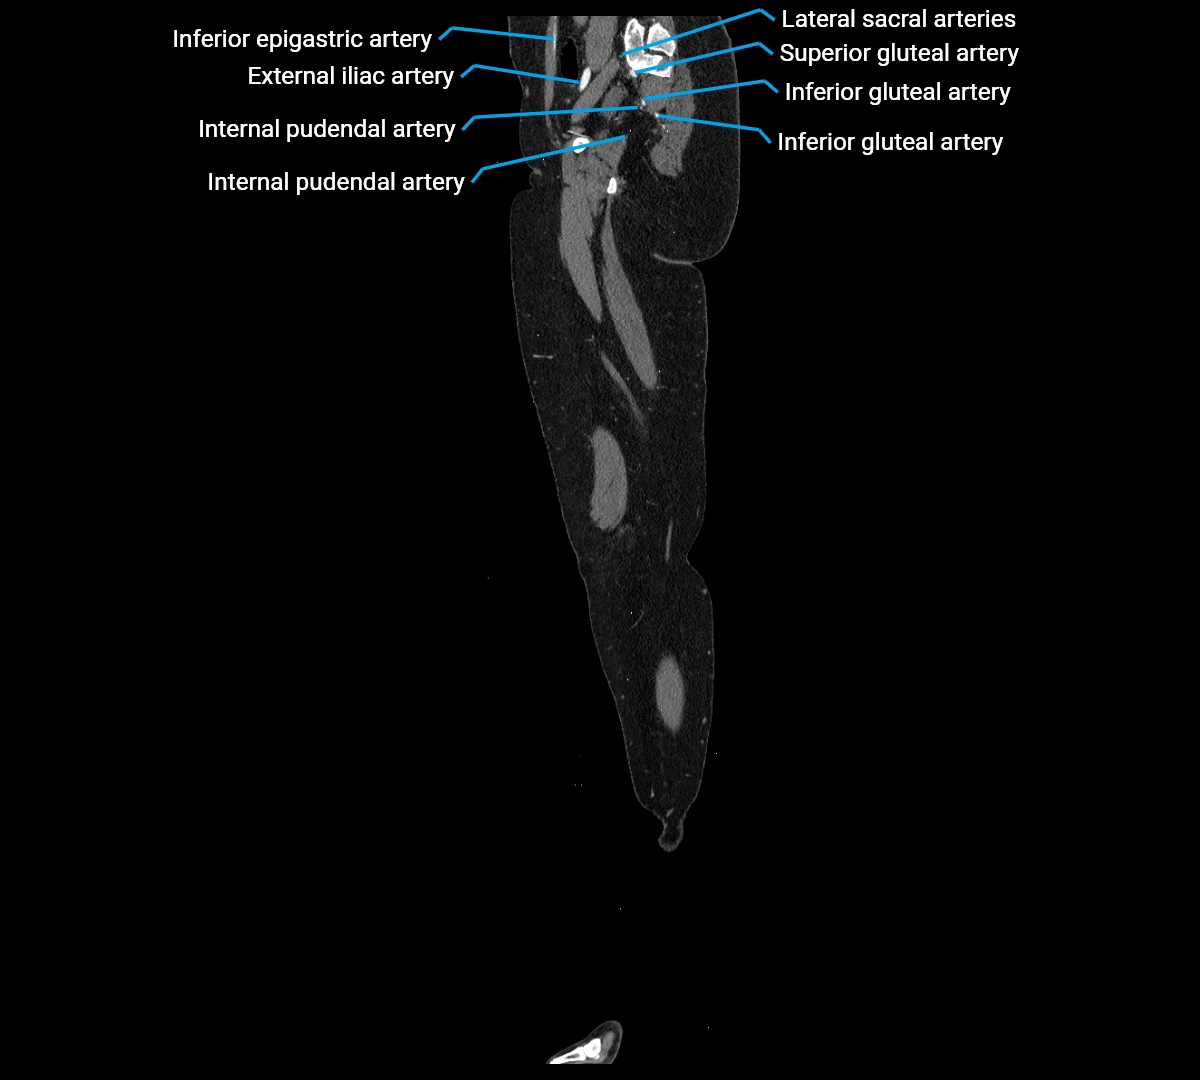

CT images

image